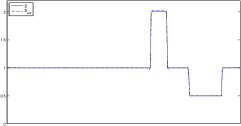

In this section, the proposed algorithm is tested on two sets of simulated two-dimensional data (with different parameter range and level of detail). We also vary the noise on the data since the reconstruction quality strongly depends on the noise level.

The data (see Figures 1 and 2) was generated in the diffusion model (1.2) using self-written (linear-basis) finite element code in MATLAB. For both examples, we took and used a uniform boundary condition . The simulated data were generated on a -grid and then down-sampled (by averaging) to to avoid inverse crime. After that, Gaussian noise with different intensities (standard deviations of and of the average signal value ) was added to the data.

The edge detector is used to detect jumps in the derivatives of the data up to second order (to obtain an initial estimate of the parameter jump set ). Since this process is highly sensitive with respect to noise, we varied the edge detection procedure subject to the amount of noise in the data. In the noise-free examples, we estimated the jumps of all three functions , that is, jumps of derivatives of up to second order. We restricted the jump estimation to for the low-noise examples (i.e., jumps of derivatives up to first order) and in the high-noise examples (only jumps in the data itself).

Reconstruction results and error profiles at different noise levels can be seen in Figures 3 and 4. In both examples, the noise-free reconstructions are very accurate and contain mostly smoothing error. In the low-noise reconstructions, due to the fact that more regularization is necessary, some of the parameter variation is underestimated. In the high-noise examples, most detail in is lost since a lot of regularization is required to get reasonable results. The fine detail in can, however, still be recovered very accurately in both examples.